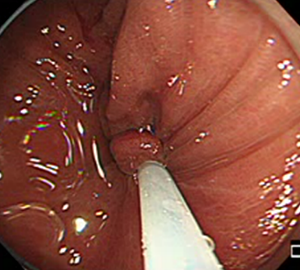

コールドスネアポリペクトミー(CSP)

合併症の非常に少ない優れた治療法であることから、近年大腸ポリープの外来切除法として急速に施行件数が増えてきています。当院ではこのコールドスネアポリペクトミーを主体としたポリープ切除を行っています。

| 1:ポリープを見つけます。 | 2:狭帯域光画像併用拡大観察で詳細に観察します。 | |

| 3:病変をスネアに通します。 | 4:周囲の正常粘膜をしっかり入れながら、病変を絞扼していき... | |